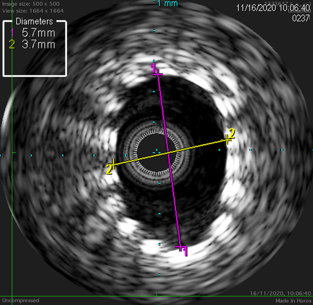

使用Sterling球囊预扩张后植入Eluvia DES的病例。IVUS评估显示,支架植入后管腔获得显著,但在支架局部不规整处最小径仅为3.7mm,提示局部扩张可能不充分。

图:支架局部不规整,最小径 3.7mm,最大径 5.7mm